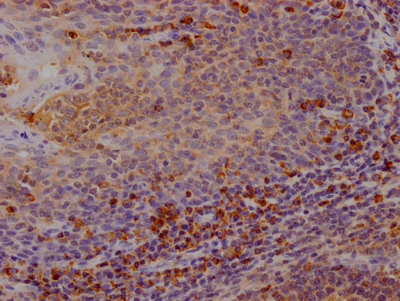

IHC image of CSB-RA213310A0HU diluted at 1:100 and staining in paraffin-embedded human tonsil tissue performed on a Leica BondTM system. After dewaxing and hydration, antigen retrieval was mediated by high pressure in a citrate buffer (pH 6.0). Section was blocked with 10% normal goat serum 30min at RT. Then primary antibody (1% BSA) was incubated at 4℃ overnight. The primary is detected by a Goat anti-rabbit IgG polymer labeled by HRP and visualized using 0.05% DAB.

IHC image of CSB-RA213310A0HU diluted at 1:100 and staining in paraffin-embedded human lymph node tissue performed on a Leica BondTM system. After dewaxing and hydration, antigen retrieval was mediated by high pressure in a citrate buffer (pH 6.0). Section was blocked with 10% normal goat serum 30min at RT. Then primary antibody (1% BSA) was incubated at 4℃ overnight. The primary is detected by a Goat anti-rabbit IgG polymer labeled by HRP and visualized using 0.05% DAB.